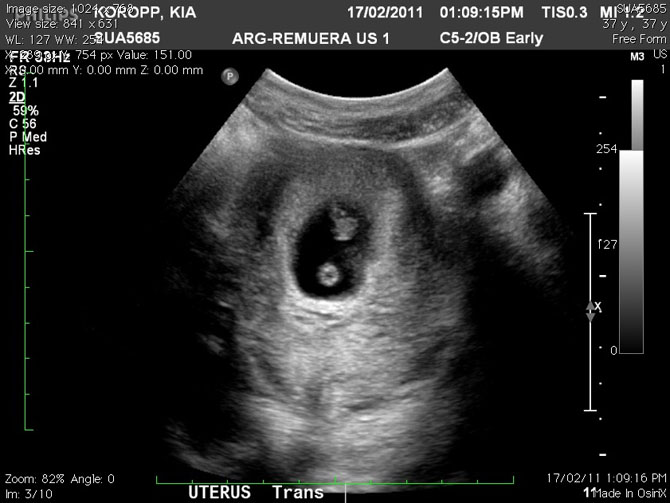

Two hours later, at 12AM, we got confirmation of a second, much smaller, addition to our adventure. Again, pictures attached for sight and feel.”